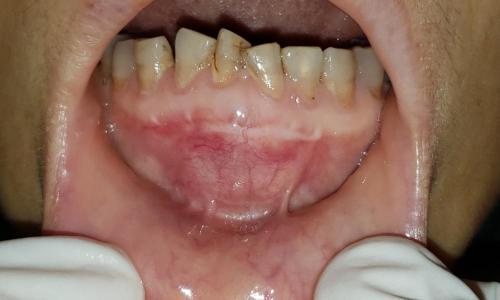

图一:患者图片

这个患者三个月前开始下前牙区肿痛,临床体查见下前牙区局部膨隆。病理活检报告:符合牙源性囊肿。